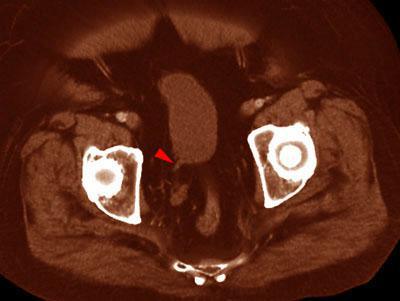

Riñón único pélvico